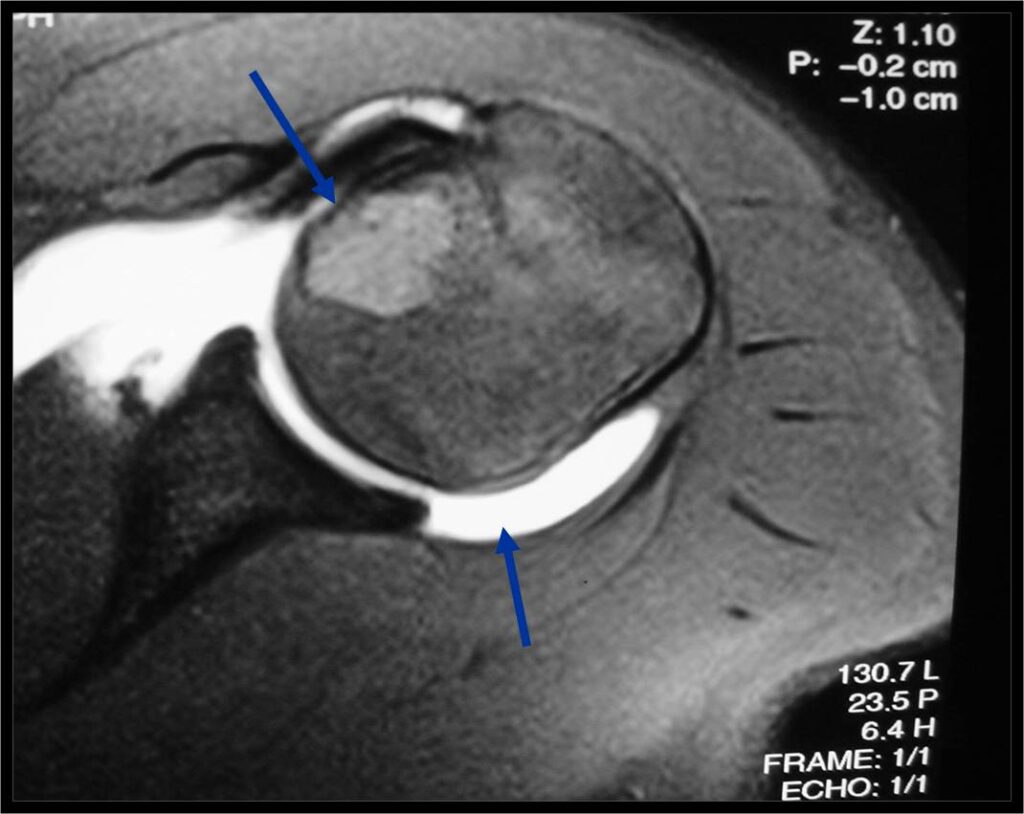

General Information Enchondroma is a benign indolent intramedullary hyaline cartilage neoplasm Accounts for 10% of all benign osseous tumors Limited growth, most lesions are less than 5 cm in maximal dimension Bones grow from a cartilaginous growth plate that...